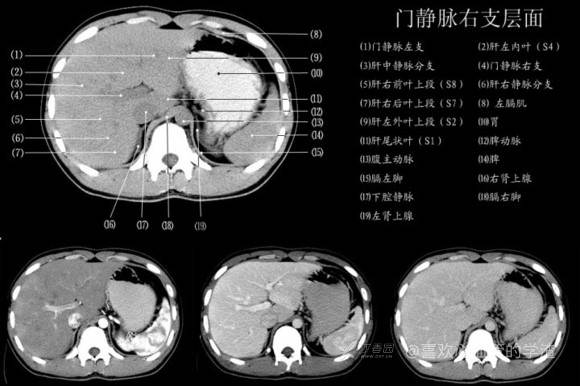

其实你离掌握上腹部 CT 影像只有一套高清实用图谱的距离,下面把我最喜欢的这本图谱分享给大家,为了方便阅读,我加了中文标识。后面附赠几张血管相对位置解剖关系图片,帮助大家理解(文中多图,建议在 wifi 环境下查看)。